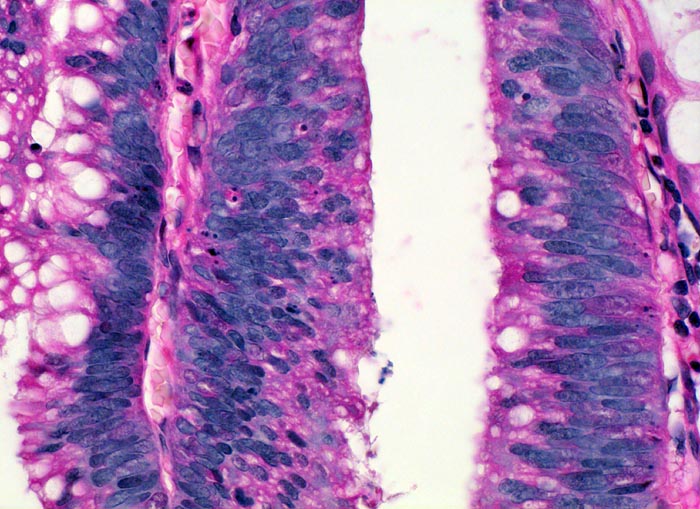

Adenom mit leichter Epitheldysplasie

Die Epithelkerne stehen sehr dicht und überlagern einander. Die Kern-Zytoplasma Relation ist zu Gunsten des leicht abgerundeten hyperchromatischen Kerns verschoben. Die Kerne sind nicht ausschliesslich basalständig, sondern wandern richtung Lumen. Die Schleimproduktion ist deutlich vermindert. Anstelle von Becherzellen finden sich lediglich kleinere intrazytoplasmatische Schleimvakuolen. Kerntrümmer von apoptotischen Zellen zeugen von einem erhöhten Zellumsatz.

Koloskopie wegen positivem Haemocculttest. Ein 5mm grosser gestielter Polyp im Colon descendens wird abgetragen.

Innerhalb eines Adenoms kann die Epitheldysplasie an verschiedenen Stellen unterschiedlich schwer ausgeprägt sein. Entscheidend für die Einteilung ist der höchste Dysplasiegrad innerhalb eines Adenoms. Aus diesem Grund und zum Ausschluss von invasiven Anteilen werden Kolonschleimhautadenome vollständig eingebettet und histologisch untersucht.

400